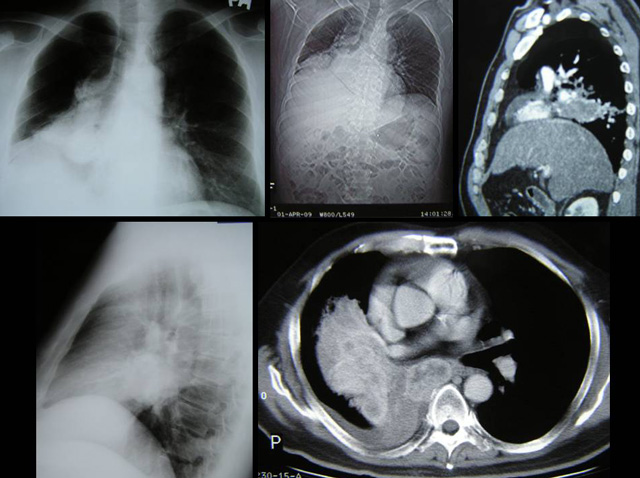

• But a CT scan done on 1 April 2009 showed the mass had increased in size from 5 x 5 x 7cm to 4 x 11.5 x 6 cm. The lymph node increased (?) from 2.5 x 4.5 x 6 cm to 3 x 3 x 4 cm. Impression: Features are suggestive of progressive enlargement of the right hilaar mass with lymph nod metastasis. Suspicious right main pulmonary artery thrombosis.

• A CT scan on 4 September 2009, i.e.,  after about four months on Sutent – showed the right lower lobe is much smaller now …  measures approximately 5 x 4.4 cm.  Impression: Left renal cell carcinoma with lung metastases post nephrectomy and chemotherapy showing good response to chemotherapy as evidenced by significant reduction in size of the lung metastases.